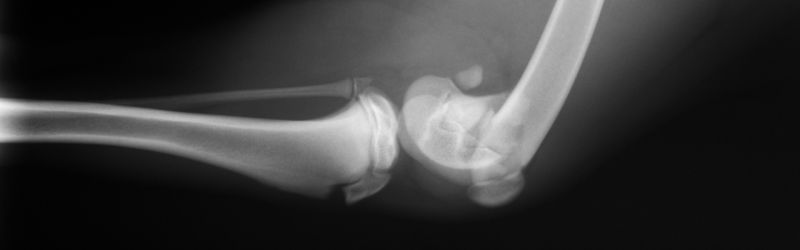

Dijagnostikovanje preloma ferume

Lekari dijagnostikuju prelom butne kosti fizičkim pregledom povređene noge, rendgenskim snimcima i CT skenirom (kompjuterske tomografije) . Ovi testovi pomažu zdravstvenim radnicima da identifikuju vrstu slomljene butne kosti. U nekim situacijama lekar može zatražiti i snimak magnetne rezonance (MR) kako bi dobio jasnu sliku eventualnih oštećenja okolnih tkiva.

Tipovi slomljene butne kosti uključuju:

• Poprečni prelom: Prelom ide pravo preko butne kosti u horizontalnoj liniji.

• Spiralni prelom: Prelom se spiralno vrti oko butne kosti.

• Kosi prelom: Prelom ide preko butne kosti pod uglom.

• Usitnjeni prelom: Postoje tri ili više slomljenih komada u butnoj kosti.

• Otvoreni ili složeni prelom: Butna kost je slomljena i komadići slomljene kosti probijaju kožu.